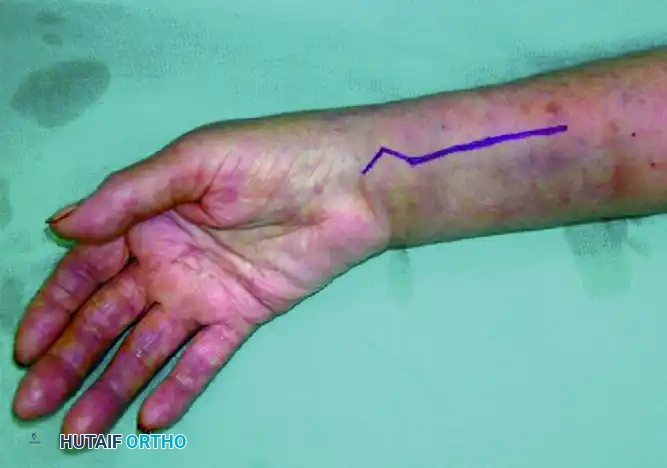

Incision and Superficial Dissection: A longitudinal incision is made over the course of the FCR tendon, extending proximally from the wrist crease.

FCR Sheath Release: The incision is carried down through the subcutaneous tissue to the FCR sheath. The sheath is incised longitudinally, and the tendon is retracted ulnarly to protect the median nerve.